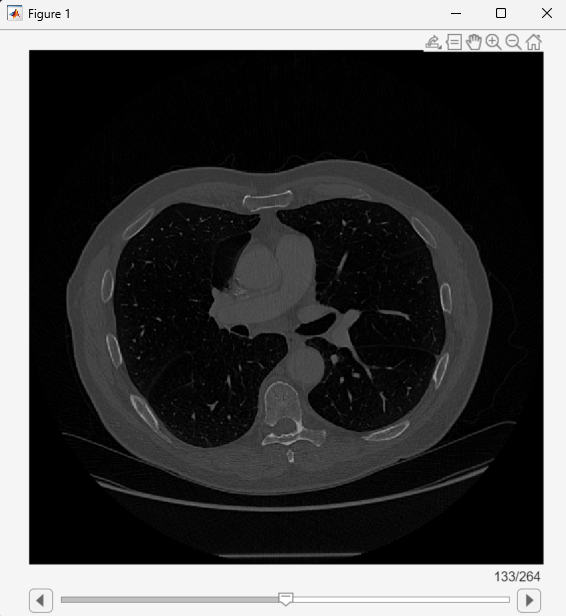

View the medicalVolume object using sliceViewer, which opens a new scrollable window that displays transverse slices.

sliceViewer(medVol)